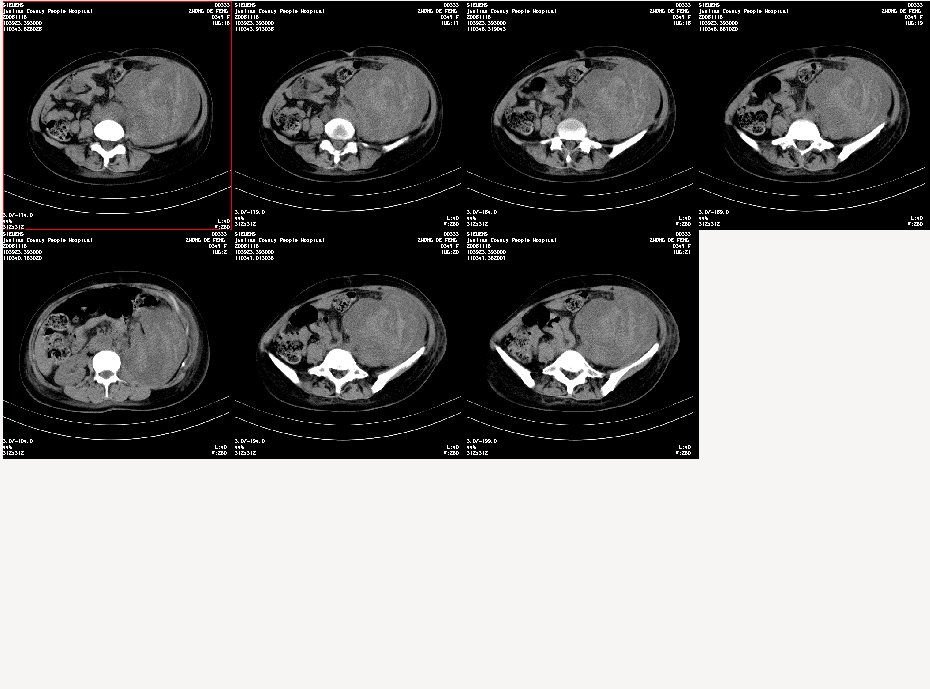

女,34岁,发觉腹部包块1周,查体:腹膨隆,左腹自肋下至髂嵴扪及10x8cm左右包块,触痛明显,固定

病变自脾下至盆腔,范围广泛,左肾显示不清,似向前内侧推移,考虑病变来源于腹膜后;病变边界不清恶性可能性大;建议增强进一步明确。

平扫病灶密度不均匀,病灶内可见条样高密度影,边清。该病例未见增强。

根据平扫密度不均匀,其内条样高密度影,考虑来源于腹膜后;

到三级医院增强结果出来了,是腹主动脉瘤破裂出血,血肿形成。